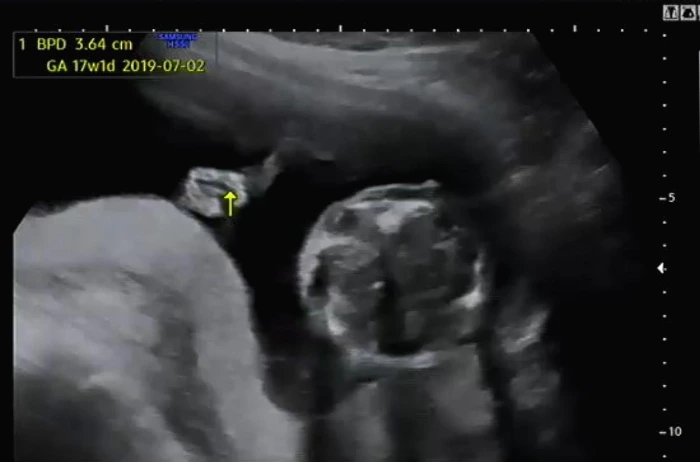

BPD(태아의 머리둘레)와 AC(태아의 복부둘레)를 측정하고 이후 심장소리를 확인했다. BPD와 AC로 이용하여 주수에 맞게 잘 자라고 있는지 확인했다. 아기는 여전히 잘 자라고 있다고 일정하게 심장소리를 들려주며 초음파 상으로 열심히 움직이고 있었다.